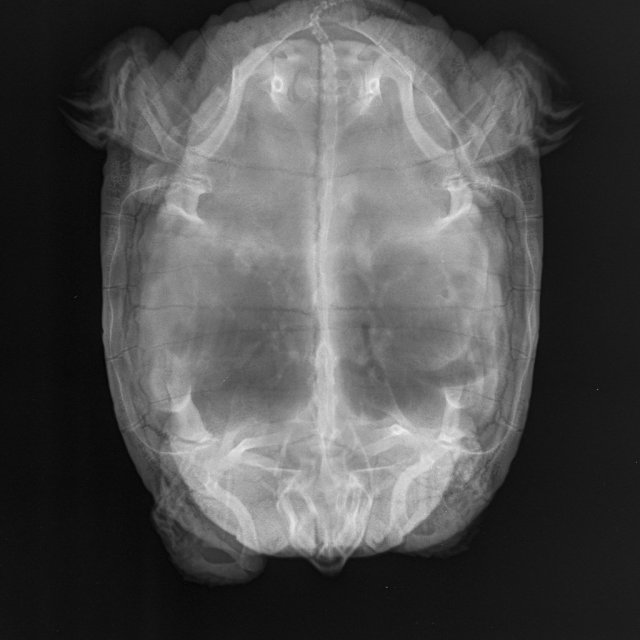

Я из Москвы, мне 49 лет. Черепаха красноухая, 10 лет, вес 1 кг 700 гр. живёт в аквариуме большом, есть лампа УФ и накаливания (включены целый день, меняем раз в полгода), есть фильтр внешний, нагреватель, мостик, грунта нет. Очень вялая - целый день отдыхает или спит, есть особо не хочет - рептомин не ест, грудку или печень раз в 5 дней после уговоров может съесть порцию небольшую, меньше чем её голова. Заметили болезнь уже недели три назад, две недели делали уколы. Последний укол 16 апреля. Прокололи курс лекарств по совету герпетолога - Кальций борглюконат через день,  Витам (1 раз в 3 суток), дексаметазон, фуросемид. По старому рентгену герпетолог сказал, что возможно яйца жировые, по свежему рентгену он никаких яиц не видит. Сейчас ничего больше не назначили нам. Я очень за черепаху волнуюсь

Рентген 2 нед назад (2).JPEG

Рентген 2 нед назад.JPEG

Рентген 2 недели назад.JPEG

по симптомам нужно исключать/подтверждать анемию и проблемы с печенью. К сожалению дистанционно тут ничем не помочь. Вы сделали ей курс уколов кальция - если бы там была рядовая проблема авитаминоза/формирования яиц, то это бы помогло.